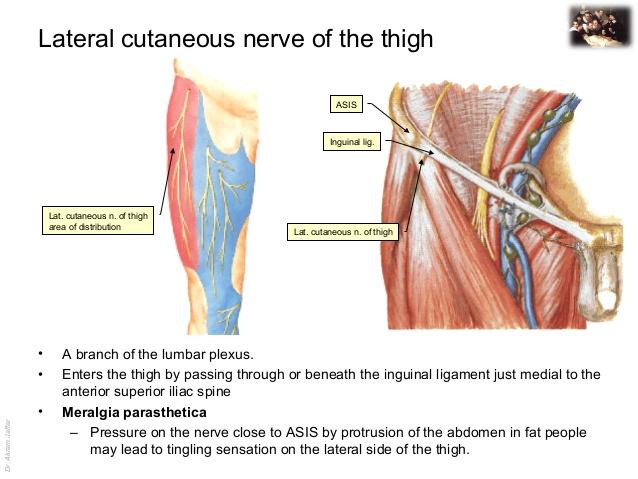

origin course and distribution of lateral femoral cutaneous nerve

O L2-L3

C emerges from the lateral border of the psoas major, crosses the iliacus muscle obliquely toward ASIS. Under the inguinal ligament, over sartorius muscle into the thigh, where it divides into an anterior and a posterior branch.

D lateral skin of thigh